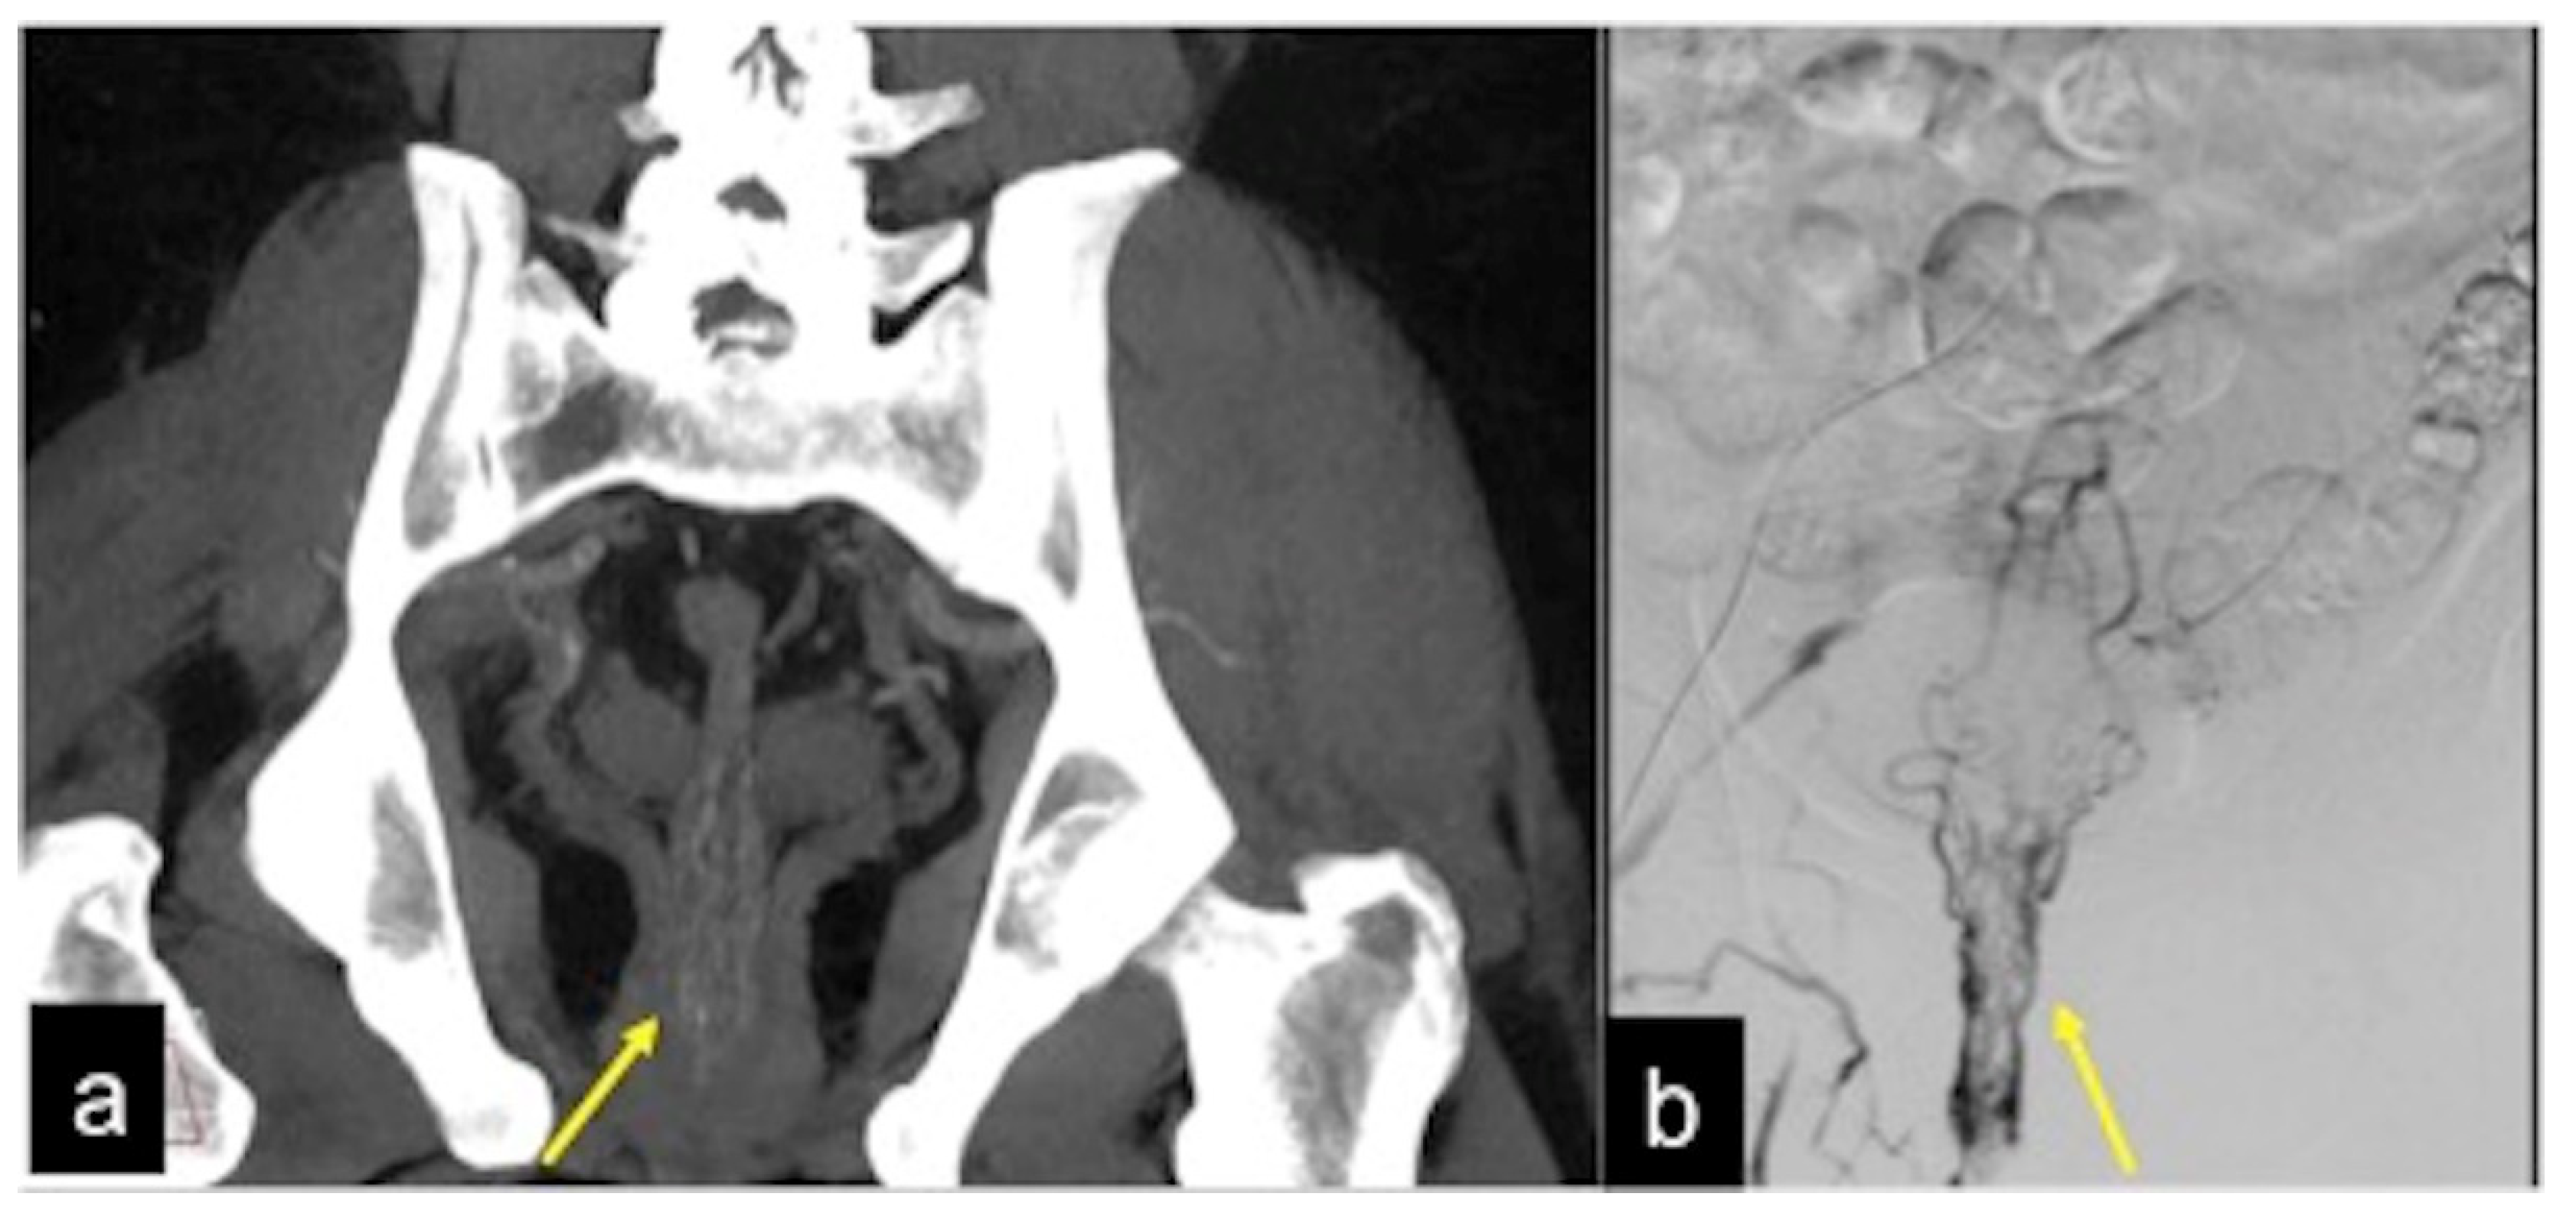

| Aorto-Enteric Fistula (Figure 31) | Bleeding in a patient with a history of surgery for aortic aneurysm. | A connection between the aorta and the intestinal lumen. Absence of adipose cleavage planes. |